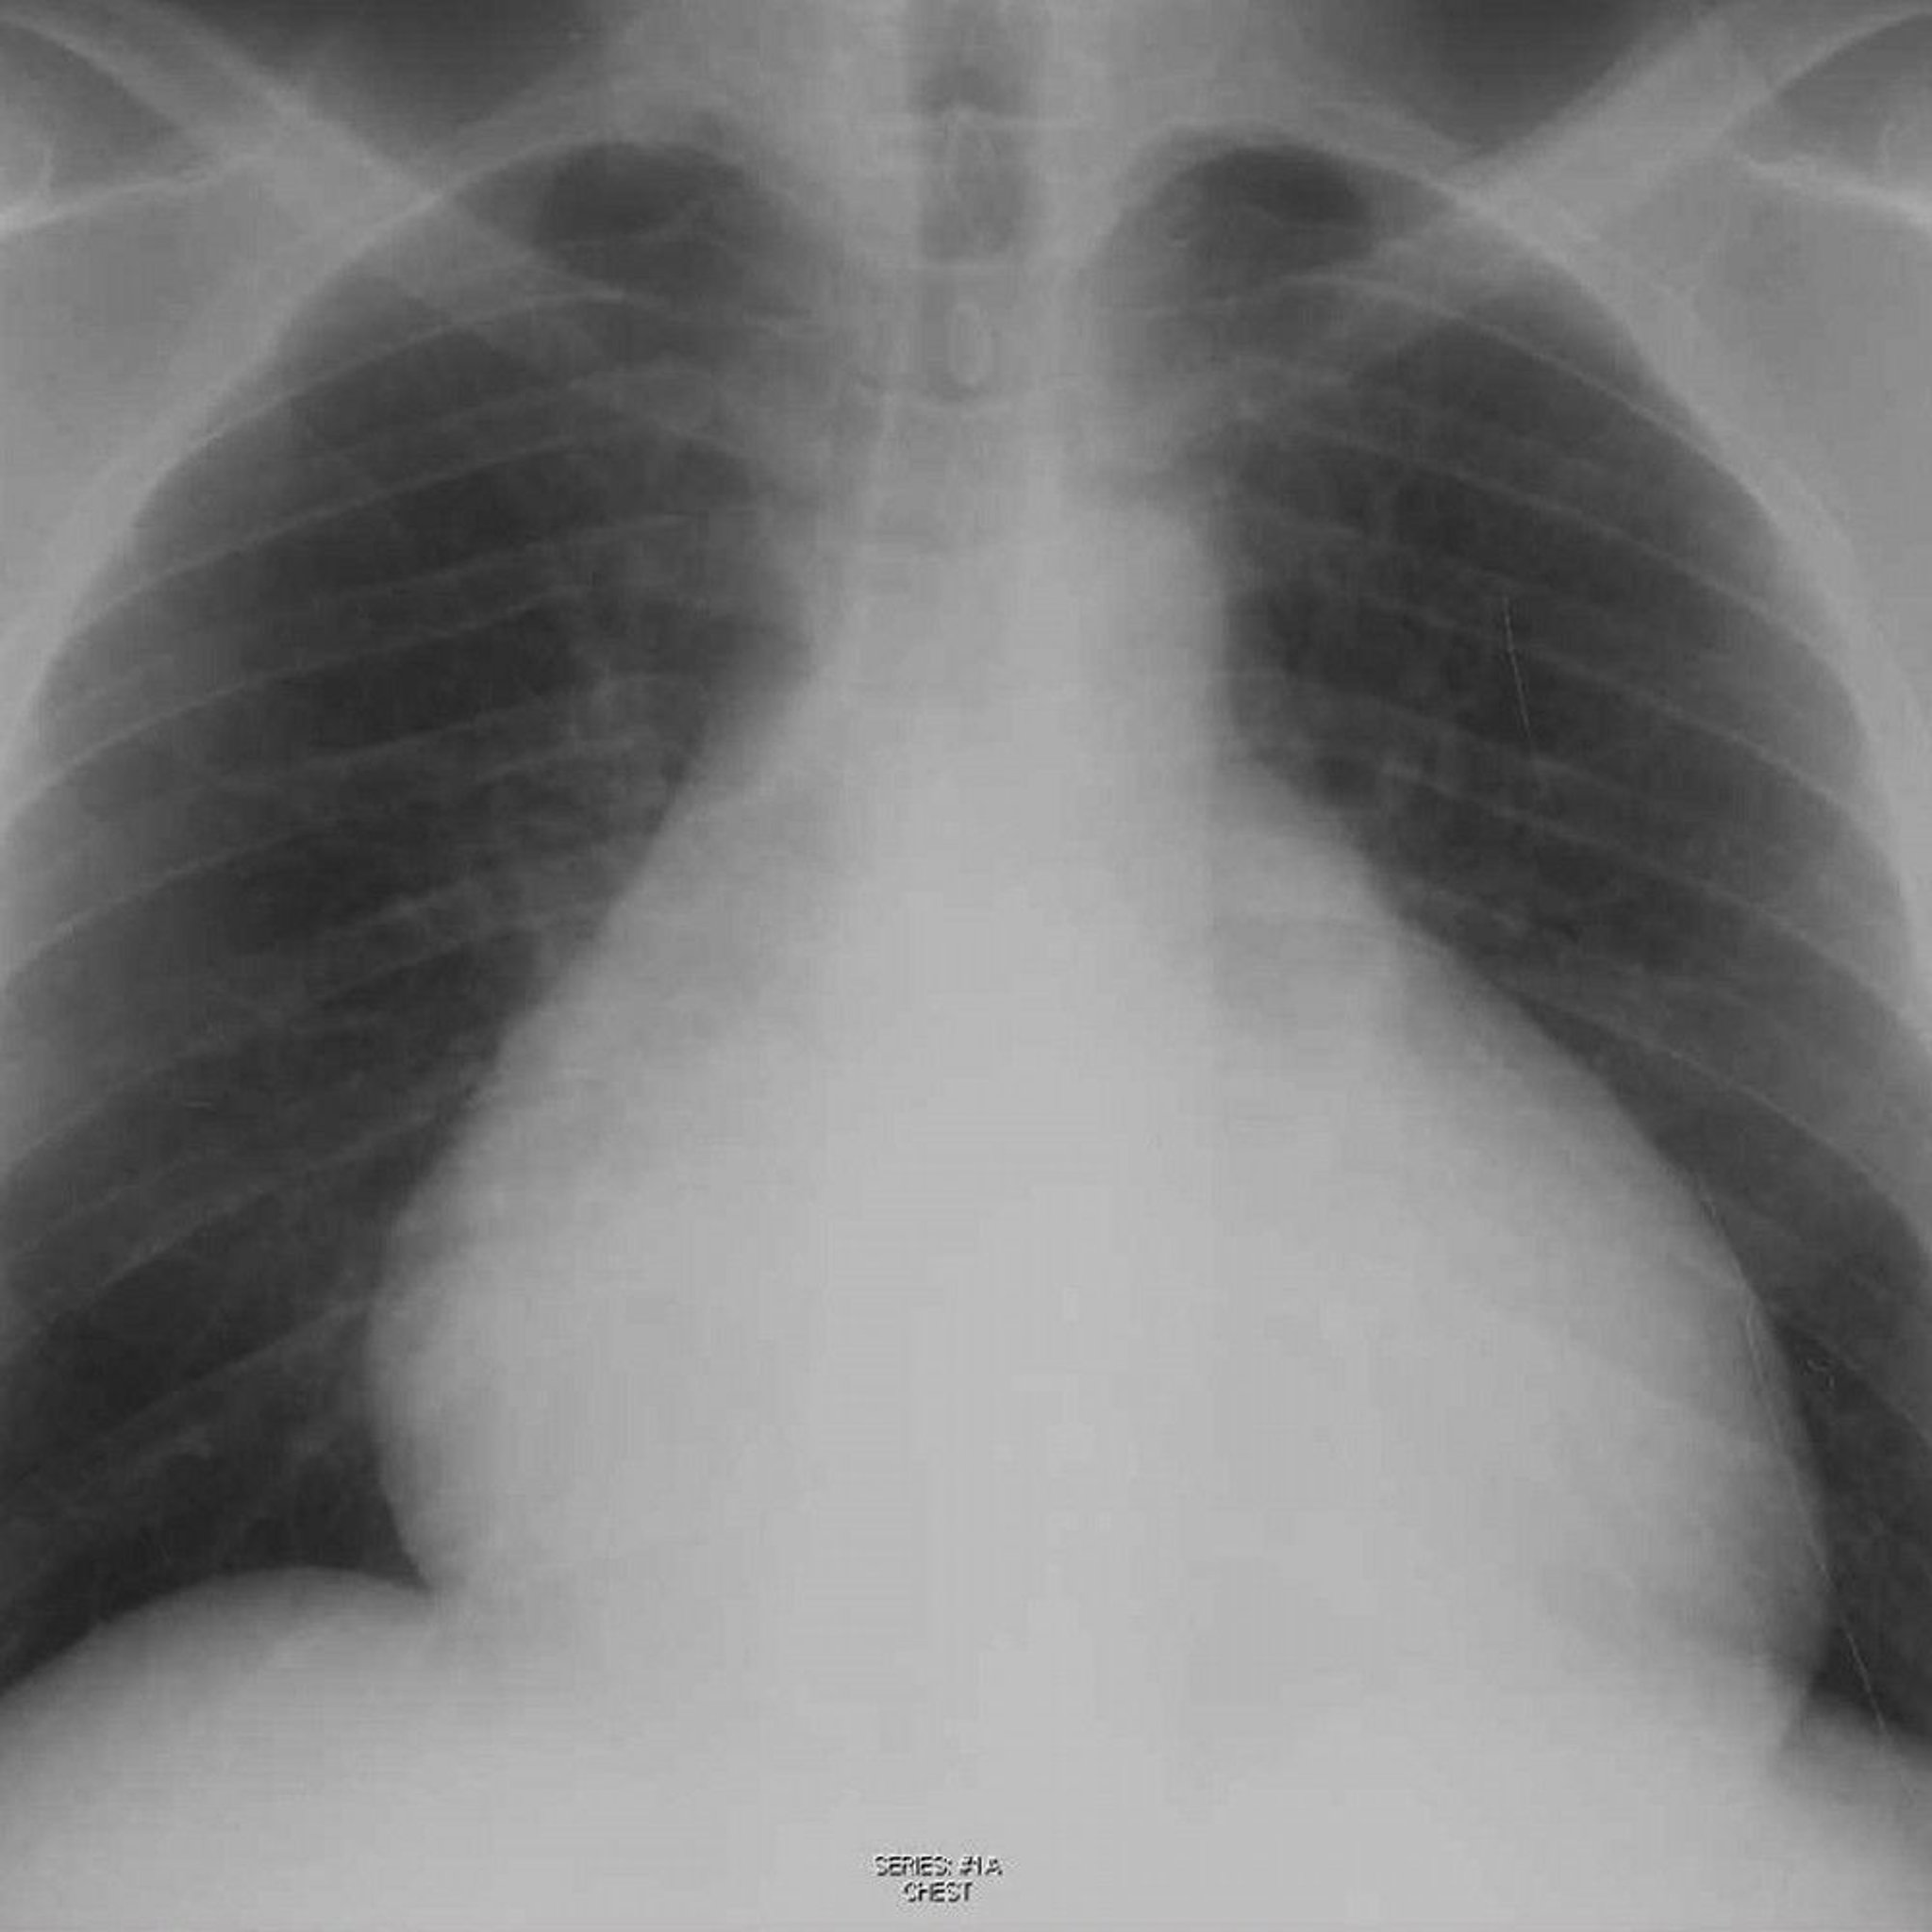

Chest Radiograph of a Patient with Pericardial Effusion

This radiograph shows enlarged cardiac silhouette in a patient with a pericardial effusion.